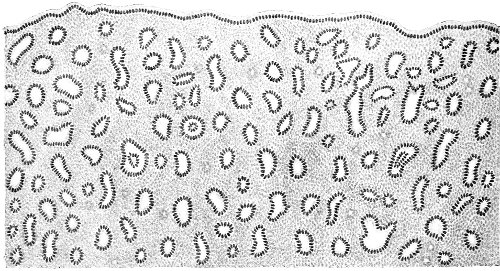

Several varieties of acute vaginitis may be recognized—the simple, the granular, the senile, and the emphysematous. It is unusual to find the entire surface of the vagina involved. The disease is confined to areas or patches separated by healthy tissue.

In simple vaginitis the inflamed membrane remains smooth.

In granular vaginitis, which is the variety usually seen, the papillæ are infiltrated with small cells, and are much enlarged, so that the inflamed surface has a granular appearance.

Senile vaginitis is due to infection of portions of the vaginal mucous membrane that have lost their epithelium as a result of the atrophic changes of old age. This disease occurs in patches of various size, sometimes presenting the character of ecchymosis; in other cases the 50 patches have altogether lost the epithelium, and permanent adhesions may take place between areas which are brought in contact. This form of vaginitis has also been called adhesive vaginitis. It is said that a similar condition may occur in children.

The emphysematous form of vaginitis occurs in pregnancy. The vaginal walls are swollen and crepitating. The gas is contained in the meshes of the connective tissue.

Acute vaginitis is accompanied by dull pain and a sense of fulness in the pelvis. The discomfort is increased by standing, walking, defecation, and urination. There is a free discharge of serum or pus, which may be tinged with blood. The character of the discharge depends upon the variety and the period of the disease. Inspection, which can best be made through the Sims speculum, with the woman in the Sims or knee-chest position, shows the characteristic lesions of inflammation of the mucous membrane.

Acute vaginitis, if neglected, may pass into the chronic form. It usually lingers in the upper part of the vagina, in the fornices, especially in vaginitis of gonorrheal origin. By careful inspection we find here one or more granular patches of inflammation, which cause a vaginal discharge from which man may be infected, and from which infection of the upper portion of the genital tract, the uterus, and the Fallopian tubes may be derived.